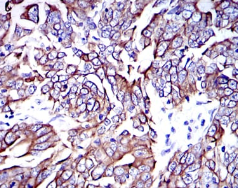

KRT19 Mouse Monoclonal antibody[4E8E3]

Species Reactivity:    Human

IHC    1/200 - 1/1000